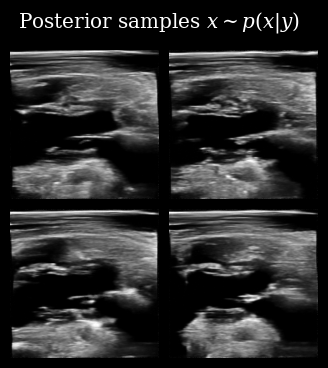

That looks correct, we now proceed with posterior sampling to generate some samples from the Bayesian posterior \(\{\mathbf{x}_t^{(i)}\}_{i=0}^{N_p} \sim p(X_t \mid \mathbf{y}_{<t})\).

[11]:

posterior_samples = diffusion_model.posterior_sample(

measurements=measurement_buffer,

mask=mask_buffer,

n_samples=n_particles,

n_steps=n_posterior_steps,

initial_step=0,

omega=10,

)

animate_samples(

posterior_samples[0],  # posterior samples has an extra batch dim of length measurements

"./task_based_posterior_samples.gif",

title=r"Posterior samples $x\sim p(x | y)$",

fps=9,

zea: Successfully saved GIF to -> task_based_posterior_samples.gif

Task Based Posterior Samples

Next we use these posterior samples to derive downstream task posterior samples, i.e. beliefs about the value of the LVID. We then compare this to the target LVID measured from the ground-truth in order to see how accurate the agent’s beliefs are.